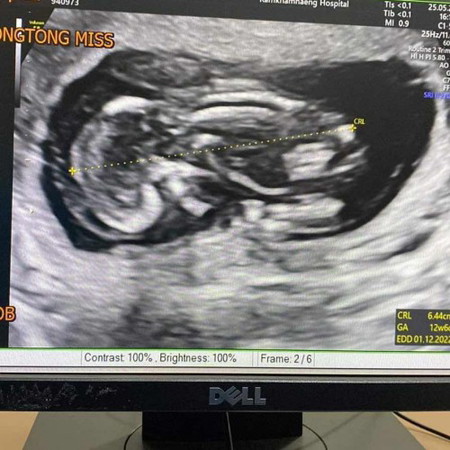

16W6D ขอวิธีทำใจหน่อยค่ะแม่ๆ 😞🙏🏻

คุณหมอนัดตรวจปกติ ปรากฎว่าตอนอัลตราซาวด์ หัวใจเด็กหยุดเต้นแล้ว หมอวินิจฉัยว่าโครโมโซมเด็กผิดปกติ เสียใจมากค่ะ 😭 ก่อนหน้านี้ก็ไม่มีอาการผิดปกติอะไรเลยค่ะ หมอนัดตรวจก็บ่อย เพราะทำงานในโรงพยาบาลใกล้มือหมอ ดูแลตัวเองค่อนข้างดี เลยไม่คิดว่าจะเป็นแบบนี้ได้ค่ะ ยังทำใจไม่ได้เลยค่ะ😞😞

อ่านเพิ่มเติมขอบคุณค่ะแม่❤️ ก่อนหน้านี้ได้ตรวจ Panorama ไปแล้วไม่มีอะไรผิดปกติค่ะ ผ่านไปอาทิตย์เดียวน้องเสีย แม่เลยทำใจยากค่ะ